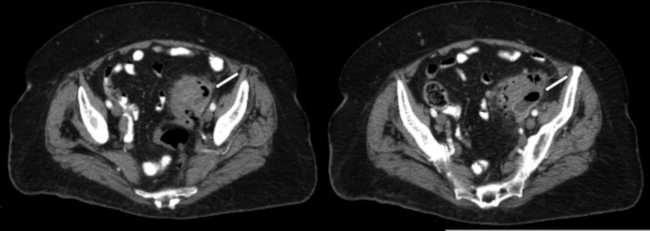

Estadio IIB: Aire distante (>5 cm del segmento intestinal inflamado). Si el paciente está estable sin comorbilidades se recomienda tratamiento conservador con eventual drenaje percutáneo guiado por imágenes; en caso contrario, resección quirúrgica con o sin anastomosis (►Fig. 7).